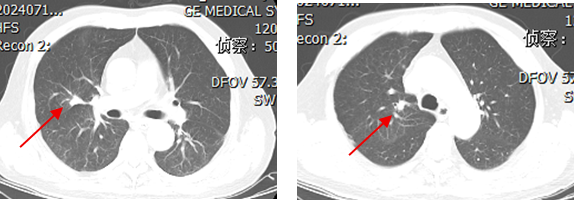

一线第2周期治疗后及4周期治疗后(2024-07-16上2024-09-11下)

1.png

2.png